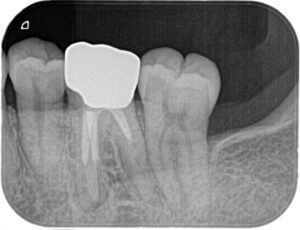

患者さんは40代女性。定期健診時に左側下顎第二大臼歯遠心に虫歯が見つかりました。

以前横向きに生えていた親知らずを抜歯しており、

おそらくその時からC1くらいのカリエスがあったと考えられますが最近になって進行してきたようです。

X線撮影を行いました。